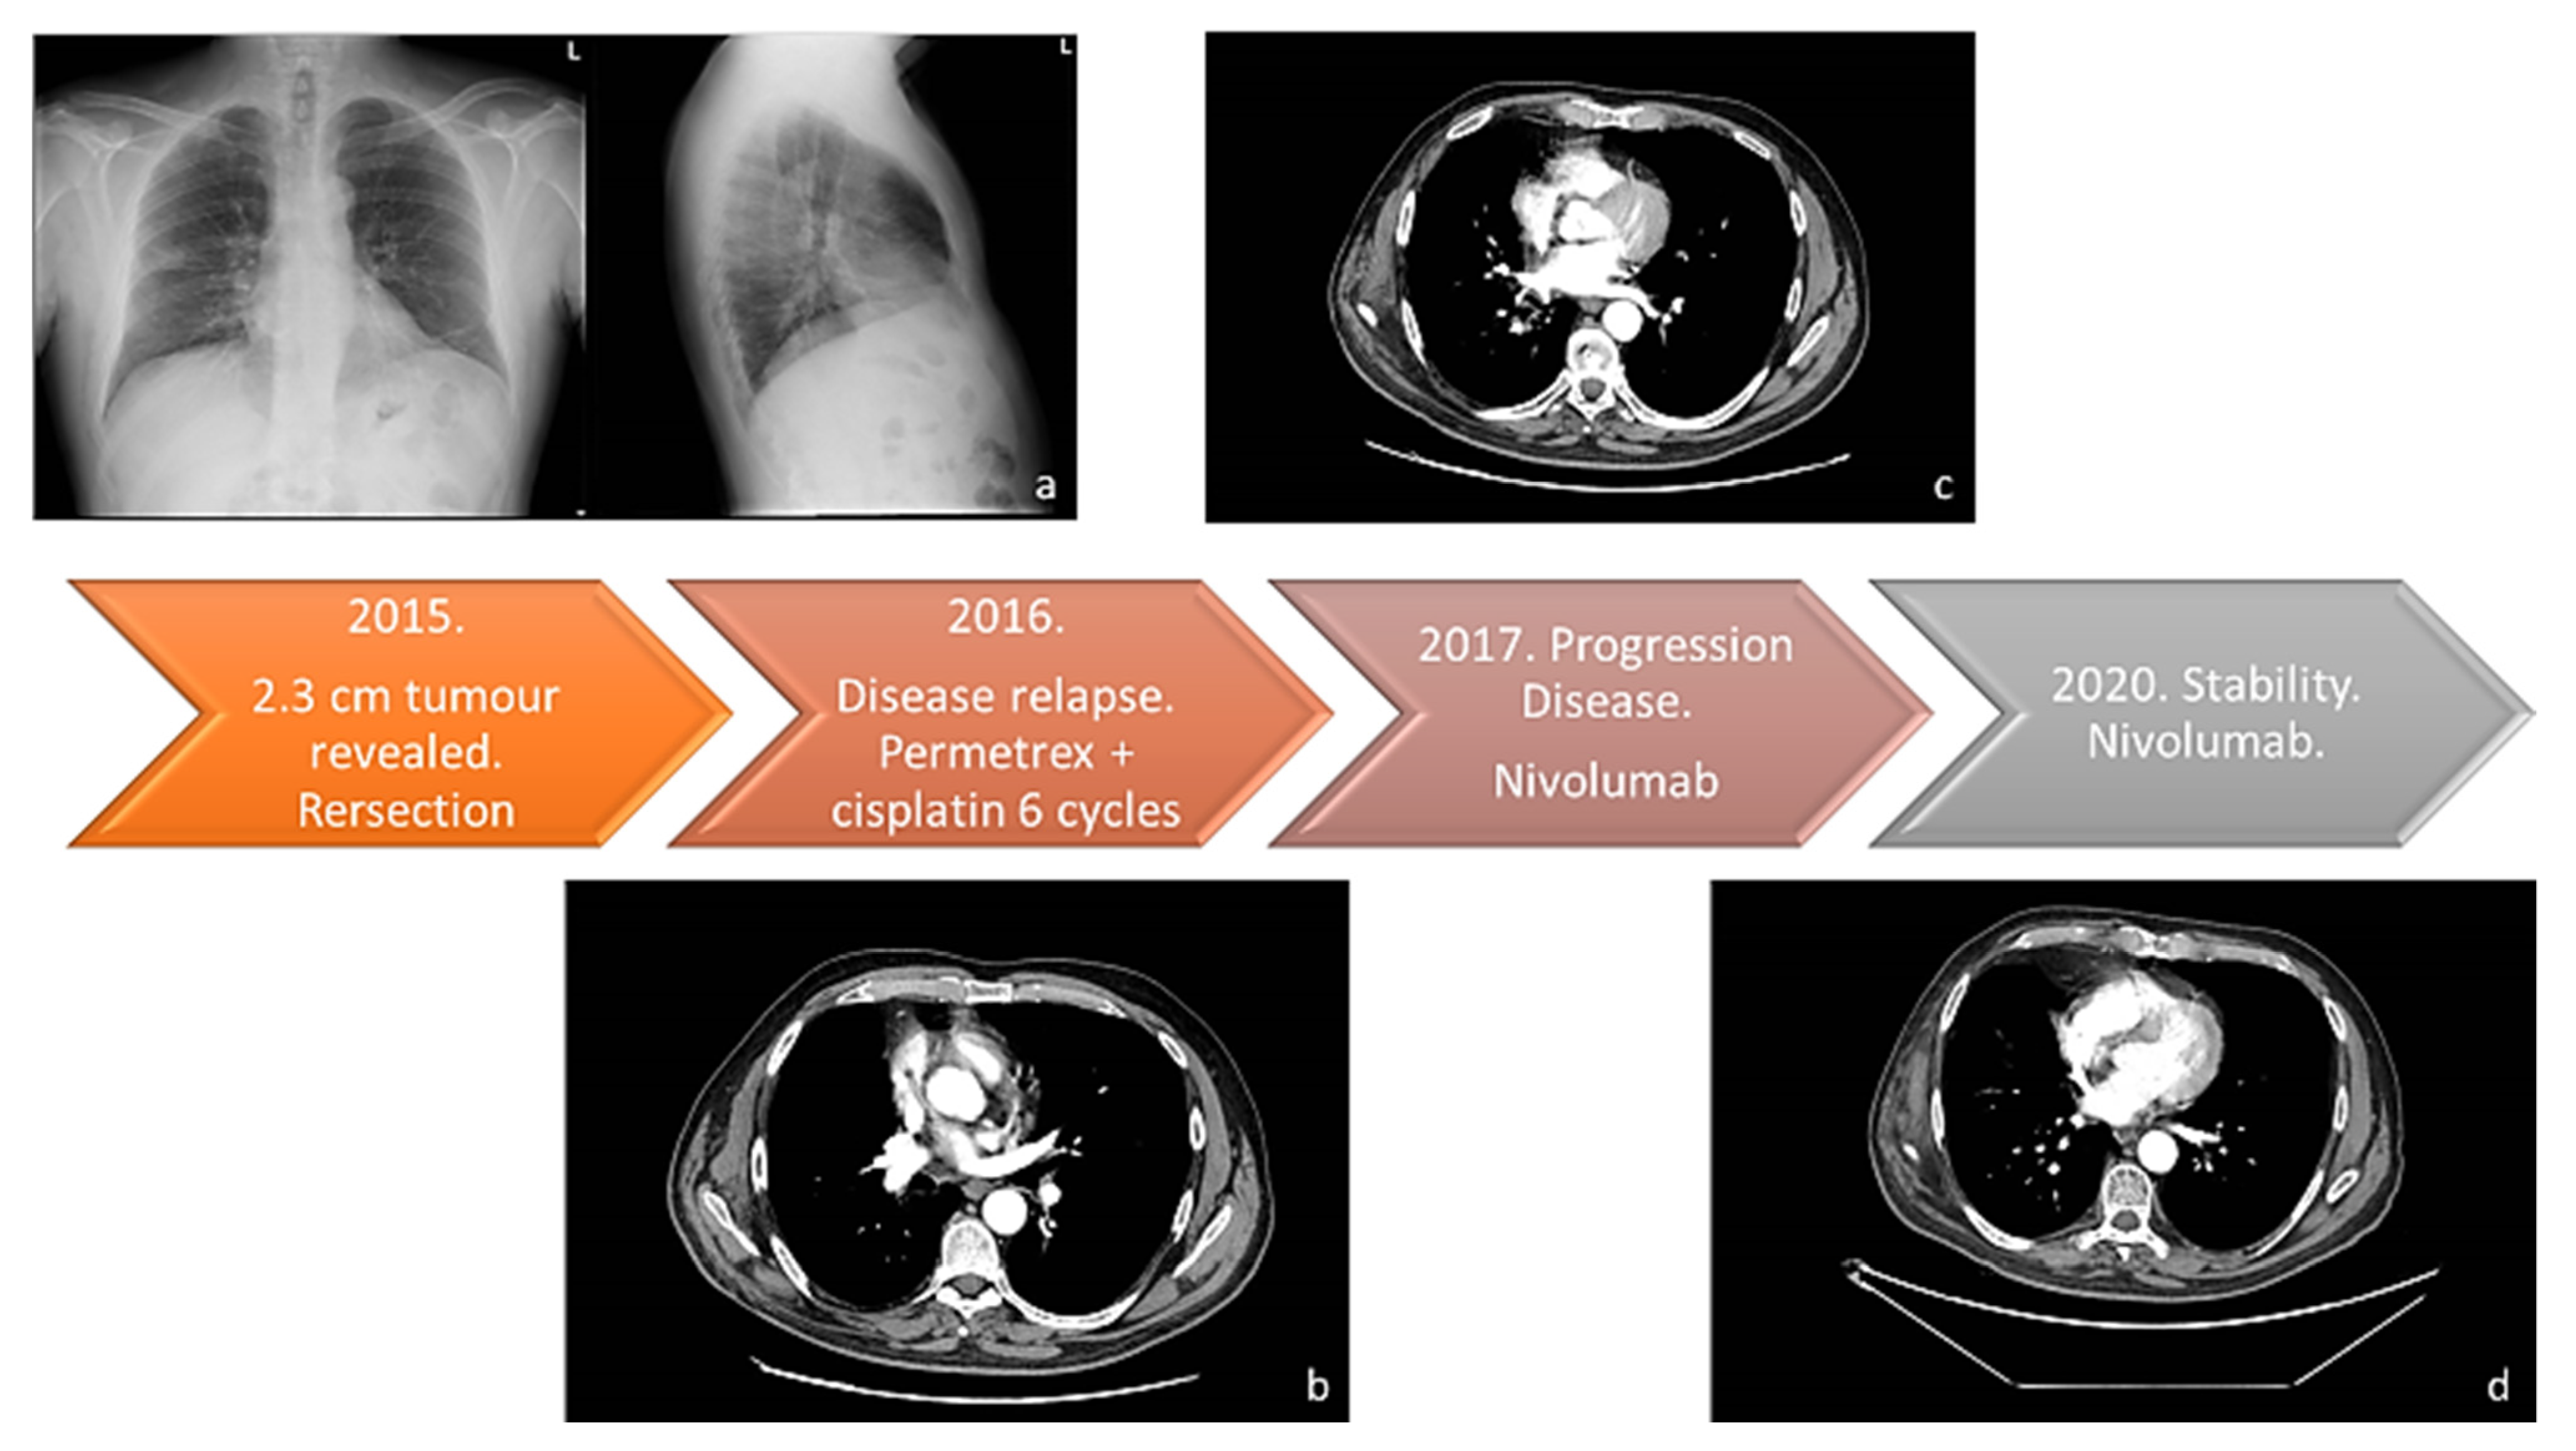

2. Case Presentation